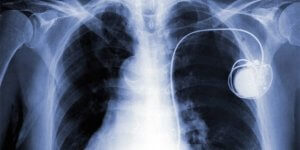

Штучним кардіостимулятором серця називається спеціальний електронний прилад. У нього вбудована мікросхема, яка дозволяє виявляти будь-які зміни в роботі серцевого м’яза. Завдяки приладу при необхідності проводиться корекція скорочень міокарда.

За допомогою коннекторного блоку здійснюється з’єднання електродів і корпусу. Електроди поміщають в серцевий м’яз, що дозволяє зчитувати інформацію про роботу серця. Несуть електричні заряди допомагають правильно скорочувати серцевий м’яз.

Важливо! Незважаючи на те, що процедура є нескладною, вся робота з встановлення кардіостимулятора проводиться за допомогою спеціального рентгенівського обладнання.

Не протипоказані флюорографію, рентген. Іноді призначається рентгенографія у разі, якщо є найменша підозра на поломку електрода.